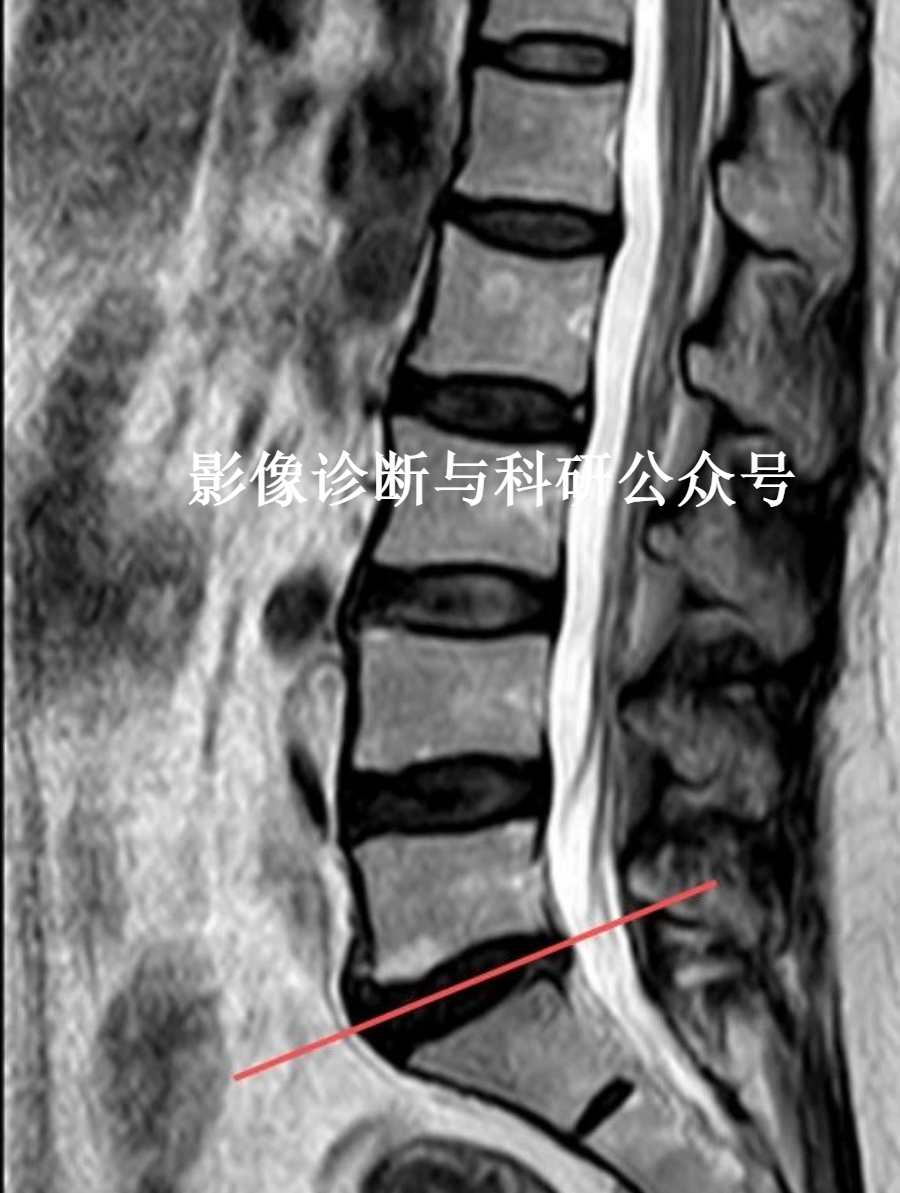

1.椎间盘退变

看T2:椎间盘信号由高变低,失去正常夹层样结构,在T2加权像上椎间盘中央信号减低明显。变性椎间盘以低信号为主,其中混杂有不规则点状高信号,高信号髓核与低信号纤维环分界消失。受累椎间隙变窄,椎间盘变薄。

椎间盘退变的Pfirrmann分级系统

磁共振成像被认为是评估椎间盘突出和随后的神经元压迫的金标准成像方式。

Pfirrmann分级系统是利用MRI对腰椎间盘退变进行分级的可靠分类系统。根据椎间盘信号强度、椎间盘结构、核与环之间的区别以及椎间盘高度,将退行性变分为5个等级。